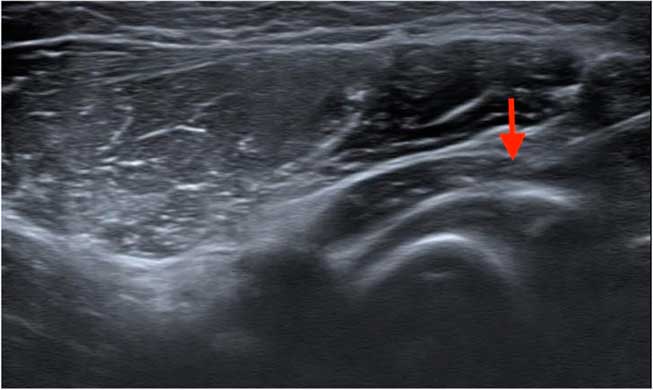

Ultrasonography was performed with an 18-MHz linear array transducer (Acuson S2000 Ultrasound System; Siemens, Munich, Germany). The probe was placed in parallel to the posterior interosseous nerve (PIN) and the PIN was examined with the forearm in the pronated and supinated positions, bilaterally, as shown in Figure 1. Compared with the right side, the left PIN showed marked compression and angulation by the superficial head of the supinator muscle in the supinated position. In-plane ultrasound-guided PIN hydrodissection was performed with a mixture of 0.5 ml 50% glucose water and 4.5 ml 1% xylocaine (Figure 2). The patient was also instructed to take oral hypoglycemic agents regularly and avoid strenuous or repetitive forearm activities.

Figure 2 Hydrodissection was performed by placing a solution surrounding the left posterior interosseous nerve through the needle tip (red arrow).